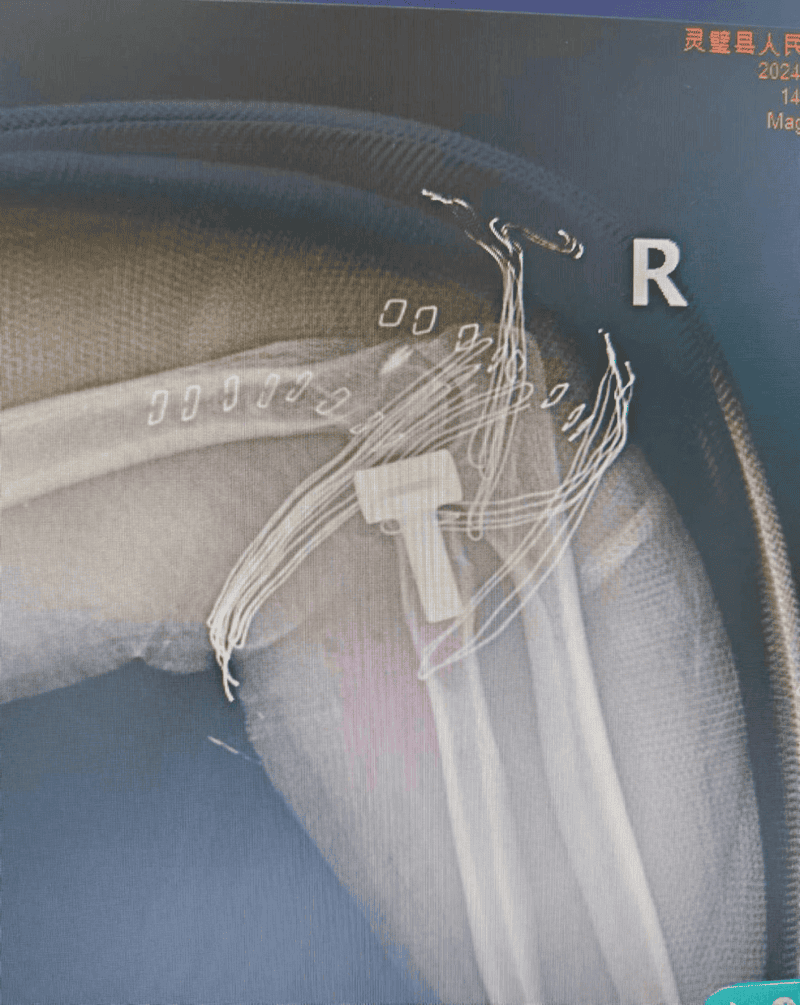

5月20日,48岁的胡女士在不慎摔倒,致右侧肘关节疼痛、活动受限。家属在当地医院行DR检查示:右侧桡骨头骨折,明显移位,入我院骨科西区住院治疗。骨科西区医生对其进行了详细的检查,根据检查结果诊为右侧桡骨头粉碎性骨折。

图为术前三维CT

骨科西区王医师第一时间为胡女士进行了手法复位及肘关节石膏固定和消肿对症治疗,以避免损伤加重。“此例桡骨头骨折为Mason分型III型,由于桡骨头粉碎程度太大,无法采用传统切开复位内固定方式,若采用桡骨小头切除术,病人因年龄较轻,后期会带来多种并发症,对患者的远期生活会带来严重的影响。术前与患者及家属沟通后,决定采用桡骨头置换术,使肘关节较快恢复到正常功能”王医师说。